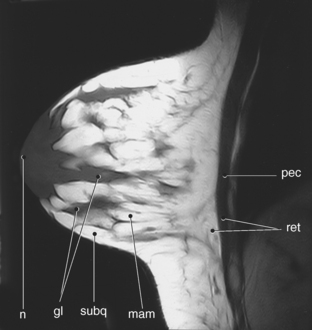

The female breast, or mammary gland, lies within the subcutaneous tissue overlying the pectoralis major muscle. Typically the breast extends laterally from the sternum to the axilla and inferiorly from the second to the seventh ribs. For examination purposes, the breast can be divided into four quadrants (upper inner, upper outer, lower outer, lower inner) and the tail of Spence (Figure 6.117). The breast consists of three layers of tissue: subcutaneous layer, mammary layer, and retromammary layer (Figure 6.118). The subcutaneous layer contains the skin and all of the subcutaneous fat. The mammary layer consists of glandular tissue, excretory (lactiferous) ducts, and connective tissues. The glandular tissue consists of 15 to 20 lobes arranged radially around a centrally located nipple. The glandular lobes are embedded in connective tissue and fat, which give the breast its size and shape. Excretory (lactiferous) ducts extend from each lobe to the nipple, where they terminate as small openings. Cords of connective tissue coursing throughout the mammary layer, from the dermis to the thoracic fascia, are known as the suspensory ligaments of the breast or Cooper’s ligaments. These ligaments provide support for the breasts. The retromammary layer contains muscle, deep connective tissue, and retromammary fat (Figures 6.119 and 6.120).

Figure 6.119 Sagittal, T1-weighted MR scan of female breast.

Key: pec, Pectoralis major muscle; ret, retromammary layer; mam, mammary layer; subq, subcutaneous layer; gl, glandular; n, nipple.

Figure 6.120 Axial, T1-weighted MR scan of female breast.

Key: ret, retromammary layer; mam, mammary layer; subq, subcutaneous layer; gl, glandular.